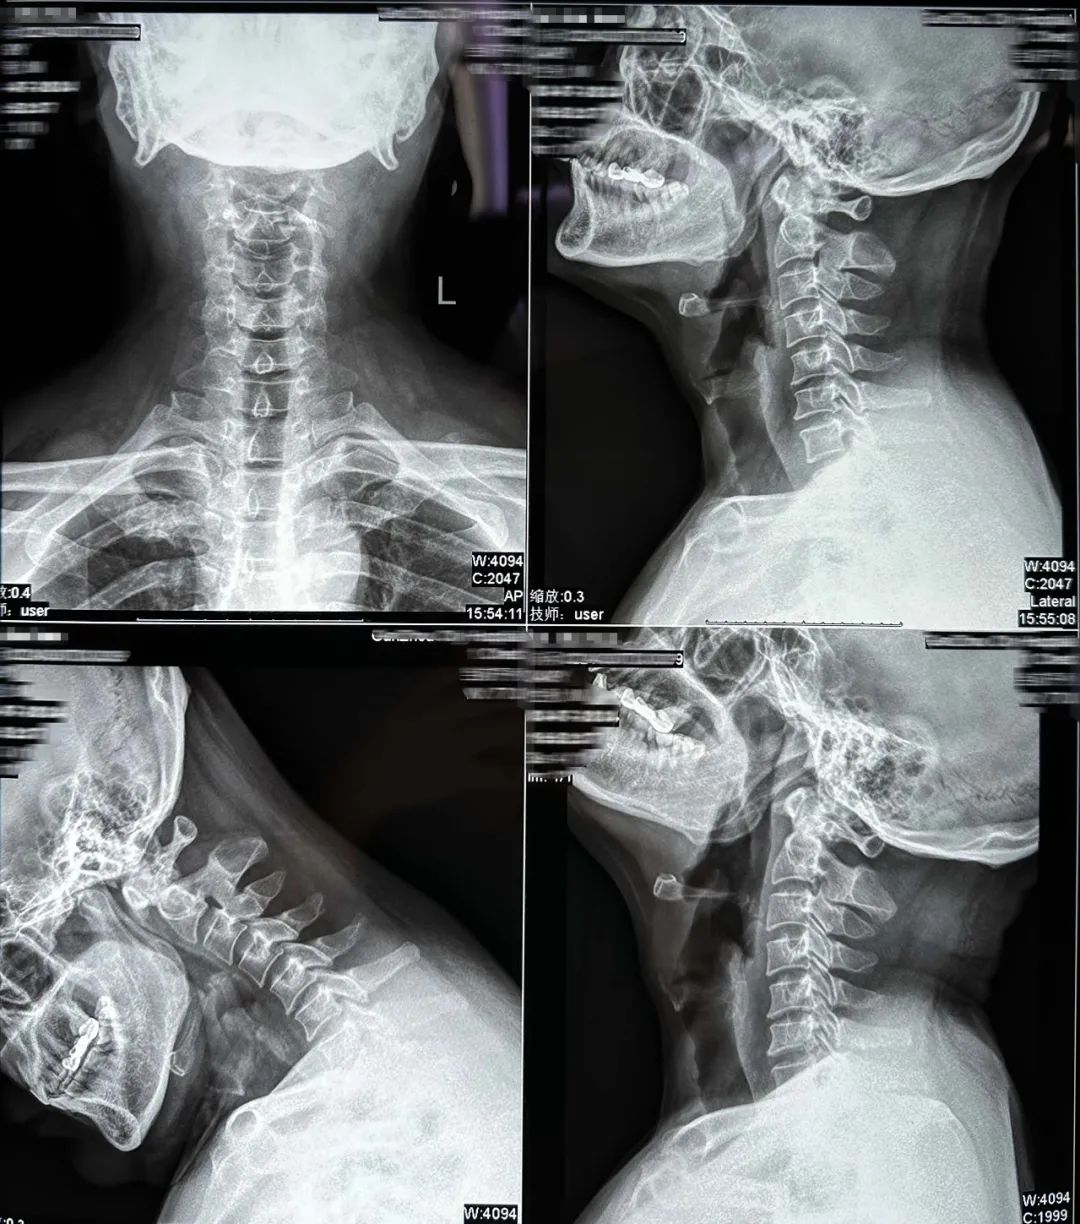

術(shù)前影像

MRI:頸椎

CT:頸椎間盤(pán)突出,伴椎管狹窄

術(shù)前診斷:

1.頸椎間盤(pán)突出(主診斷)

2.混合型頸椎病